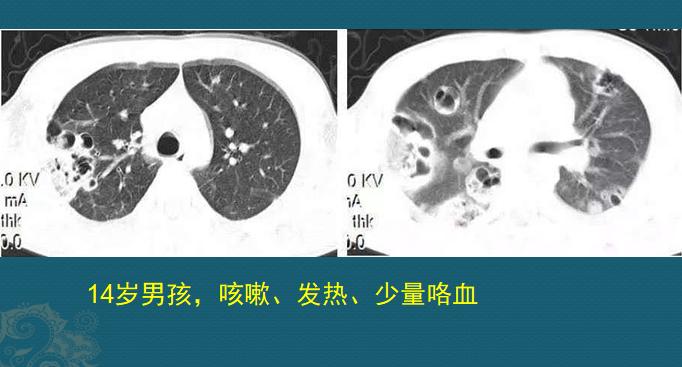

我们通过下面这个病例,看一下它贪、钻的特性:

下图是另一位病人,春节期间在家隔离,坐久了腰背痛,就到针灸推拿店做了针灸,结果几天后开始发高烧,考虑是皮肤消毒没做好,金葡菌沿着针孔侵入皮下筋膜和肌肉组织内,发生了右侧竖脊肌、髂腰肌和髋周脓肿,细菌还沿着血管入侵肺部,引起肺部金葡菌肺炎,小空洞形成:

图2有小空洞

这位病人后来做血液培养找到金黄色葡萄球菌,使用敏感抗生素治疗后好转,住院20多天,总算控制住感染好转出院了。